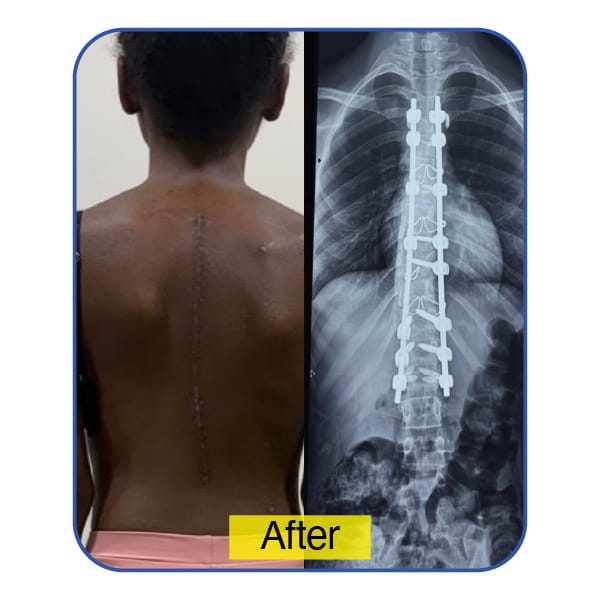

A 14-Year-Old from Seychelles – From Isolation to Empowerment

Severe scoliosis had significantly impacted this teenager’s posture, school attendance, and social life. As the curvature progressed, so did her emotional distress and withdrawal from activities she once enjoyed.

Through meticulous surgical planning and deformity correction, spinal alignment was restored, posture improved, and her self-esteem rebuilt. She is now confidently re-engaging with school, friends, and daily life empowered and pain-free.